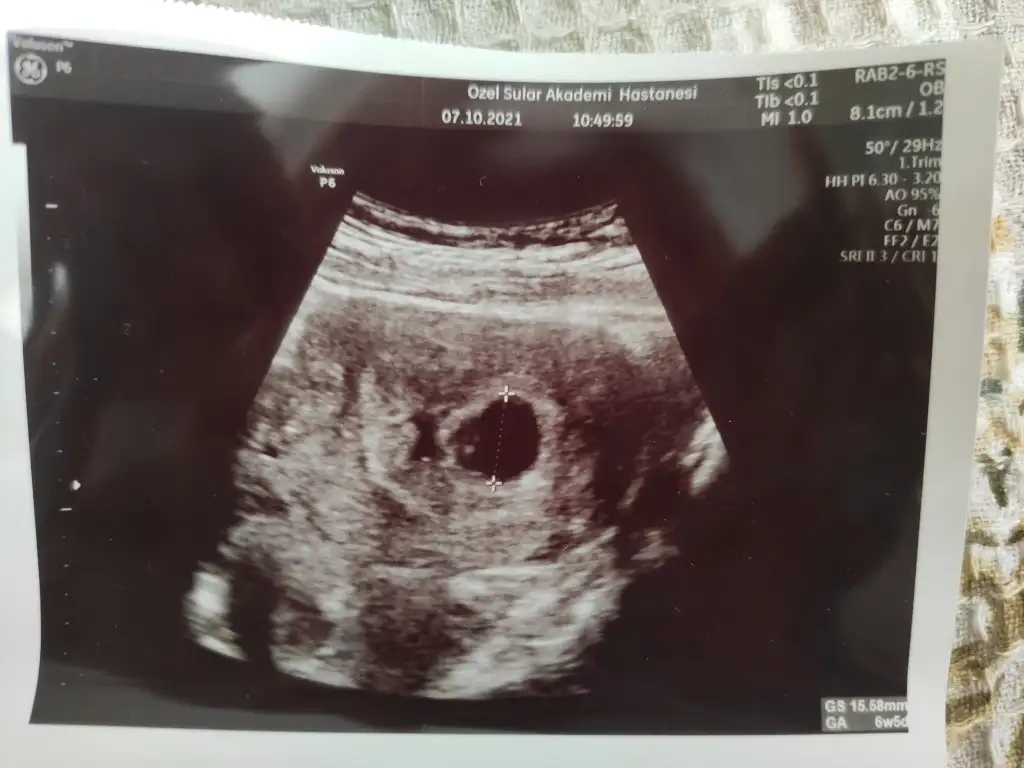

Kızlar benim ultrason resminde iki kese var ama doktor ikinci keseden hiç bahsetmedi, normal mi acaba bilemedim

Dur bak atayım resmi sen de bak var mı yok mu

Eklentiler

• IMG_20211007_182248.webp

30,8 KB · Görüntüleme: 94